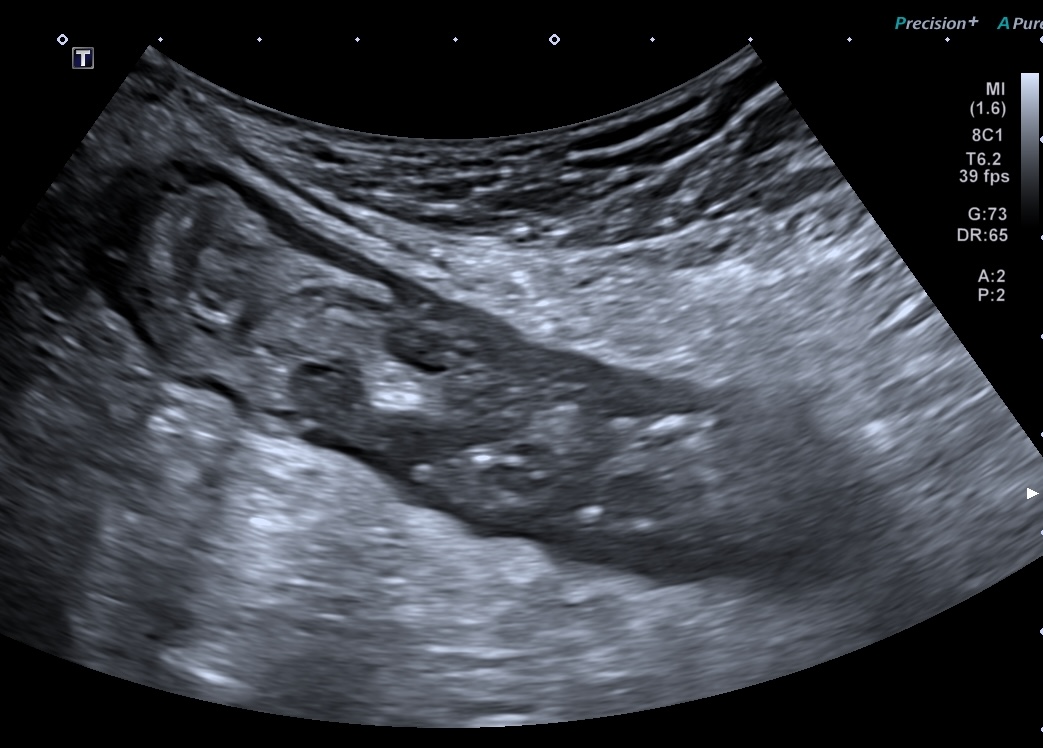

Basse Fréquence inflammation de la graisse autour du colon transverse (maladie de Crohn colique)

La graisse infammēe autour d'une anse devient hyper-échogene.

C'est un élément majeur de l'inflammation en échographie.

- Plus l'inflammation atteint la séreuse, plus la graisse environnante devient infiltrée

- plus importante en cas d'inflammation transmurale, type Crohn ou colite ischemique.